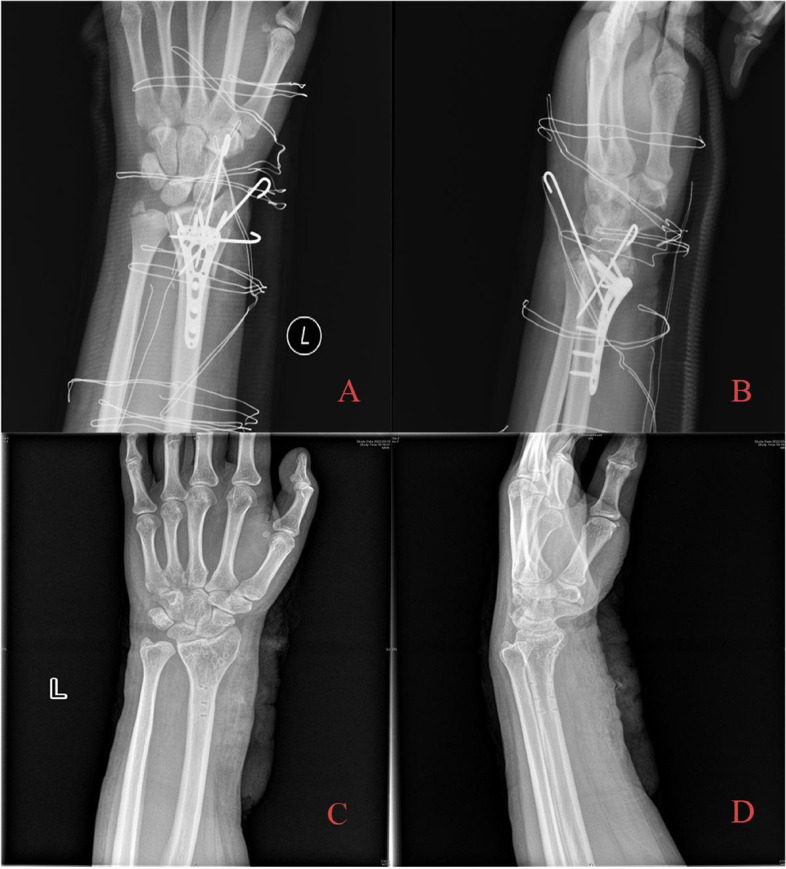

Fig. 5.

During the operation, it was found that there was a bone defect at the fracture end after indirect reduction. Allogeneic bone grafting was performed, Kirschner wire was used to fix the free bone fragment, and VLP was used to fix the fracture. A Immediate postoperative AP radiography; B Immediate postoperative lateral radiography; C AP radiography after 18 months of follow-up. Radial height was well maintained, and the articular surface was congruent in general; no obvious articular step-off developed. D Lateral radiography after removal of internal fixation